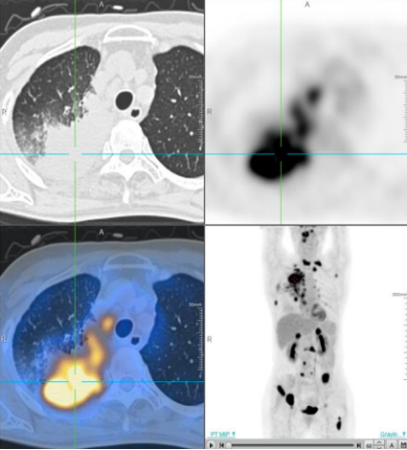

• 2024-09-04 PET-CT:1. 右肺上叶伴糖代谢增高的团片状密度增高影,最大SUV值12.39,最大横截面约70.2×45.2mm,邻近支气管截断,考虑为周围型肺 MT,伴远端阻塞性肺炎;右肺上叶及下叶背段癌性淋巴管炎;双肺及双侧胸膜多发转移;右颈 VB 区、纵隔内、右肺门、左侧内乳淋巴结转移;双侧肾上腺转移;多发骨转移,伴左侧第 1 肋病理性骨折; 2. 右叶甲状腺改变;3. 左肺门非特异性炎性淋巴结可能;右侧胸腔积液;4. 肝脏钙化灶;右肾囊肿;左侧附件区良性改变;5. 左侧第3肋陈旧性骨折。

图1 2024-09-04 PET-CT图像